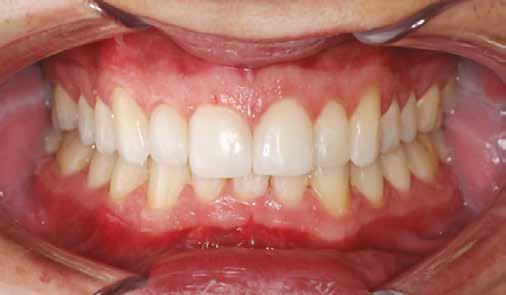

A fogászati kezelések során manapság már nem kizárólag az esztétikai megjelenés helyreállítására törekszünk. Sokszor a kedvezőtlen esztétikai megjelenés hátterében álló okok következményes módon a fogazat funkcionális működését is károsítják, így a kezelések során ezeknek a helyreállításával is foglalkoznunk kell. A különböző funkcionális és esztétikai diszkrepanciák kezelésére számtalan módszer létezik, ám ezen fogászati beavatkozások mindegyikében közös, hogy a kivitelezésük során nagyon szoros együttműködésre van szükség a kezelést végző fogorvos és a munkáját segítő fogtechnikus között. Az alábbi esetbemutatás során egy fiatal hölgypáciens fogazatának héjak alkalmazásával történő esztétikai és funkcionális rehabilitációját szeretnénk ismertetni.

A 19 éves hölgypáciens azzal a kéréssel jelentkezett a rendelőnkbe, hogy szebb fogakat szeretne. Az első konzultáció alkalmával megkérdeztük, hogy mi zavarja leginkább a fogazatának jelenlegi megjelenésében, valamint azt is megbeszéltük vele, hogy milyen végeredmény elérése esetén lenne maradéktalanul elégedett. Ebben az esetben a kezelési célokat az alábbiakban határoztuk meg:

A páciens fogazata esztétikai megjelenésének és funkcionális működésének a lehető legtöbb, saját foganyag megtartása mellett történő helyreállítása (1. és 3. ábra).

A kezelés megtervezése során kifejezett jelentősége van annak, hogy jó kommunikáció legyen a páciens, a fogorvos és a fogtechnikus között. A páciens leendő fogazatának természetes megjelenését a kezelésben részt vevő team szakmai felkészültsége, gyakorlati tapasztalata és a kezelés sikerességének irányába történő elkötelezettsége biztosítja. A beavatkozások megkezdése előtt megtörtént a páciens anamnézisének a felvétele, valamint a klinikai kivizsgálását is elvégeztük. Ezt követően lenyomatokat készítettünk a kiindulási állapotról, majd a kiindulási helyzetet extra- és intraorális fotók segítségével is rögzítettük (13. a-c. ábra).